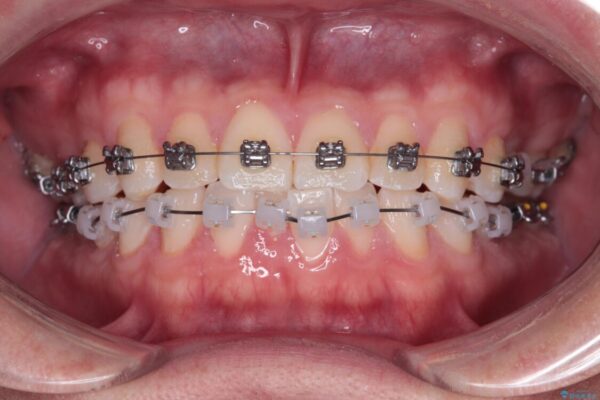

治療途中

• 前歯のガタガタ・奥歯のかみ合わせ(シザーズバイト)を改善|1年半で完了したメタルブラケット矯正 治療途中画像